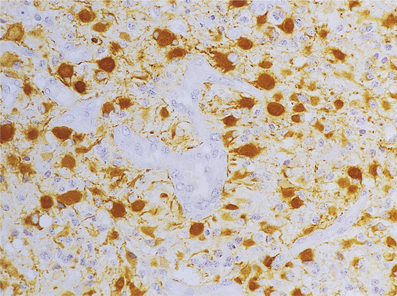

Human immunodeficiency virus (HIV) infection

The CNS is commonly involved in HIV infection both in the acquired immune deficiency syndrome (AIDS) and in pre-AIDS stages. The mechanisms by which HIV gains access to the CNS are uncertain; many research workers believe that the virus is carried across the blood–brain barrier in monocytes or macrophages (the ‘Trojan horse’ theory). Once in the CNS, the virus appears to reside predominantly in microglial cells and multinucleate cells of the macrophage/microglial type (Fig. 26.16). Evidence for direct infection of nerve cells and other glia is not fully established and awaits further research.

image

Fig. 26.16 Giant cell encephalitis in AIDS. The giant cells (arrows) in the cerebral cortex are derived from macrophages which are infected with HIV and express viral proteins on the cell surface.

Patients with HIV infection frequently present with neurological abnormalities and at the time of death at least 80% of AIDS patients have CNS pathology resulting from:

cerebral HIV infection (causing progressive dementia)

multiple opportunistic infections (e.g. Toxoplasma, fungi)

other viral infections (e.g. cytomegalovirus, papovavirus)

primary cerebral lymphoma (p. 785).

Other organisms important in infecting immunosuppressed patients are listed on page 770. Dementia may occur in the absence of overt immunodeficiency (i.e. AIDS); diagnosis can then be made by serology on the blood, or by PCR analysis of CSF.